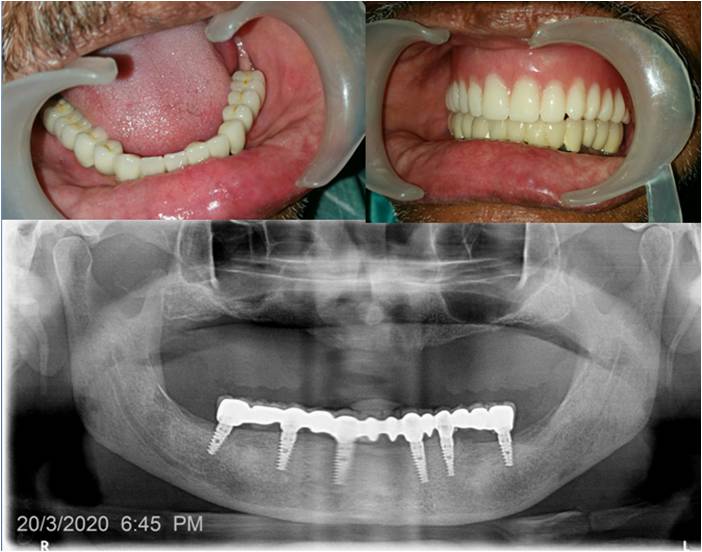

We are a team of 3 certified dentists specialised in offering the best dental treatments in town. With adequate experience of over 17 years, we have mastered the skills of offering the best solutions with the latest technologies.At Sri Durga Specialty Dental Clinic, we are dedicated to providing top-quality dental care in a comfortable and friendly environment. Our team of experienced dentists and staff use the latest technology and techniques to ensure the best outcomes for our patients. From routine check-ups to advanced dental procedures, we offer a comprehensive range of services to meet all your dental needs. We pride ourselves on our patient-centered approach, focusing on personalized care and building lasting relationships.

Cosmetic Dentistry

Dr. T. Harshavardhan Reddy, MDS, is an esteemed Oral Physician and Implantologist committed to delivering exceptional dental care. With extensive expertise and a patient-focused approach, he ensures top-quality treatment for all.